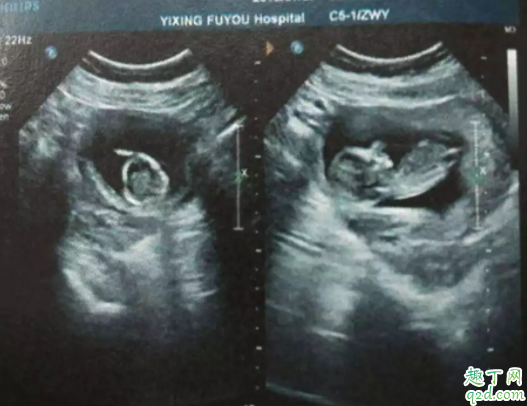

如果孕酮值較低,但無陰道出血和腹痛癥狀,彩色多普勒超聲顯示胎兒正常,則無需擔心,心理壓力也是導致流產(chǎn)的因素之一。早期流產(chǎn)最常見原因是胚胎或胎兒染色體異常,只有少數(shù)患者因激素缺乏所致。